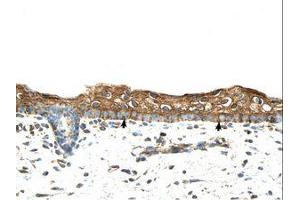

Cet anticorps anti-RBPMS Polyclonal Lapin (ABIN320529) détecte spécifiquement RBPMS dans WB, IHC et IHC (p). L’anticorps est réactif avec des échantillons de Humain, Rat, Souris, Chien, Boeuf (Vache), Cobaye, Cheval, Lapin, Singe, Roussette (Chauve-souris), Poulet, Porc et Xenopus laevis.

Western Blotting (WB), Immunohistochemistry (IHC), Immunohistochemistry (Paraffin-embedded Sections) (IHC (p))

Approved: IHC, IHC-P, WB